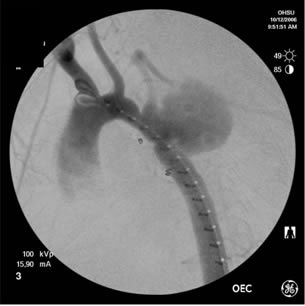

THORACIC AORTIC SYNDROMES Traumatic Aortic Rupture, Aortic Aneurysm, Aortic Dissection, Intramural Hematoma, and Penetrating Atherosclerotic Ulcer Stephen Ledbetter, MD, Jeffrey L. Stuk, DO, and John A. Kaufman, MD Catheter angiography has traditionally been the ... Get Doc

Repair of penetrating thoracic aortic ulcers has not pre-viously been reported. 4,5 We present two patients with ruptured penetrating ulcers of the thoracic aorta who which a penetrating ulcer of the mid-descending aorta was also (Fig 1A) revealed. ... Document Viewer

Stent Graft In Treatment Of Penetrating Thoracic Aortic Ulcer

Figure 1 A, Contrast-enhanced computed tomographic scan at level of descending aorta demonstrates wide neck posterior penetrating ulcer (arrow). ... Doc Viewer